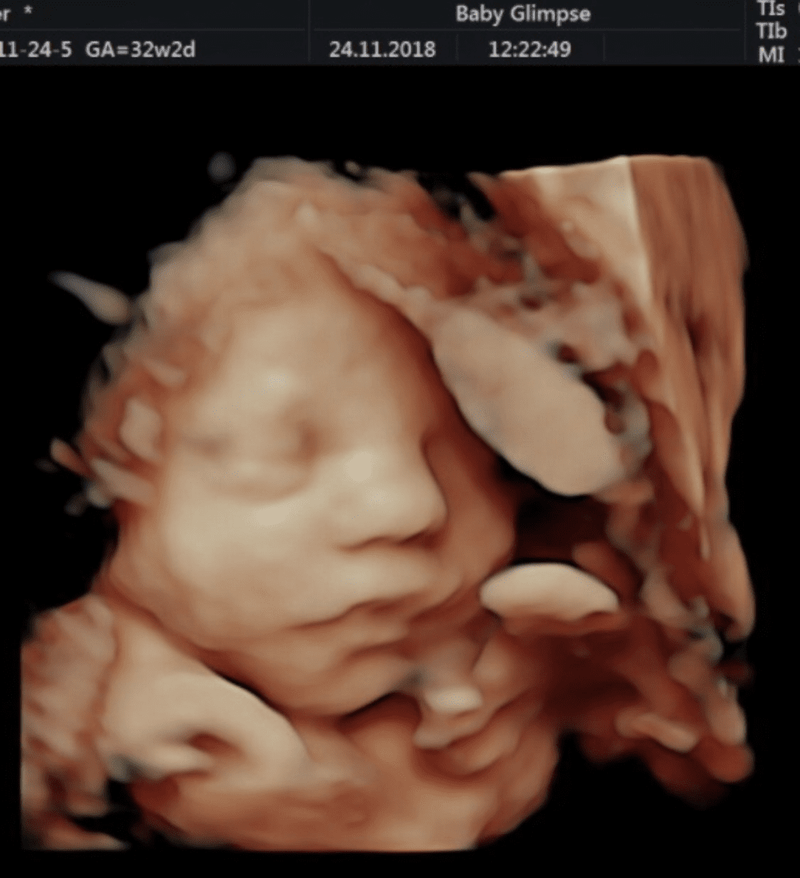

Heel eerlijk, zooooveel zwaarder dan de eerste zwangerschap. Ik weet niet of het komt doordat je al een kind hebt of het nu een jongen is, maar het is niet te vergelijken wat mij betreft. Waar ik bij Emily nergens last van had (alleen op het einde, omdat ik zo groot was), ben ik nu vanaf het begin de kwalen aan het Fvinken. Van misselijkheid tot bandenpijn en bekkeninstabiliteit. Hij is ook al vrij lang heel druk en trapt me soms m’n lichaam uit, maar dat zal ik waarschijnlijk ook wel weer missen straks als hij er is. Ik mag zeker niet klagen hoor, maar wel een verschilletje in zwangerschappen, ja!